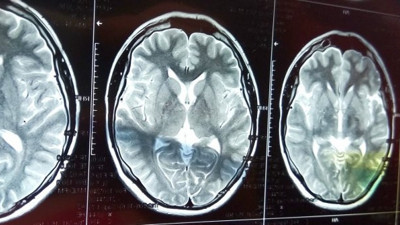

İnsan beyniyle ilgili bilinmeyen gerçekler İçerisindeki milyarlarca nöronla tüm vücudun adeta denetim mekanizması olan beynin bilinmeyen yönleri nelerdir? İşte detaylar...

Beyin tümörünün bulunduğu yere göre 20 belirtisi Birçok farklı şekilde kendini gösterebilen beyin tümörleri, bulundukları bölgeye göre çeşitli sağlık sorunlarına neden olabiliyorlar. İşte beyin tümörlerinin dikkat edilmesi gereken belirtileri.

Korona beyni küçültüyor. Karmaşık zihinsel görevler yapılamıyor Nature dergisinde yayınlanan bir araştırmayla korona geçirenler bazı hastaların genel beyin boyutunun yüzde 0,2 ile yüzde 2 arasında küçüldüğü tespit edildi.

Uzman Dr. Savaşçı'dan korkutan açıklama Ankara'da Enfeksiyon Hastalıkları ve Klinik Mikrobiyoloji Uzmanı Doç. Dr. Ümit Savaşçı, İngiltere'de yapılan araştırmayla Covid-19 geçirenlerin beyinlerinde 'gri cevher' denilen alanda küçülme ve hücre ölümü tespit edildiğini söyledi. Doç. Dr. Savaşçı, "Bu açıkçası ilerleyen dönemde hem MS hem Alzheimer artışlarına neden olabilecek bir gelişme" dedi.

Galatasaray eski başkanı Mustafa Cengiz'den bir kötü haber daha Bir süredir sağlık problemleri yaşayan Galatasaray eski başkanı Mustafa Cengiz’den üzen haber geldi. Cengiz’in çekilen MR sonrasında beyninde tümör tespit edildi.